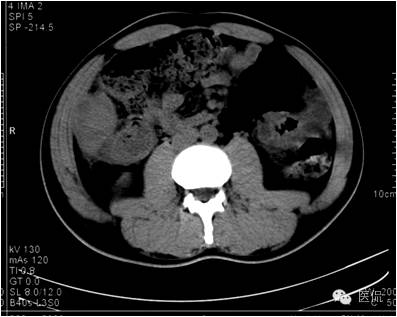

动脉期病灶显示小片状低密度影内,见不规则环状、核心样点状和间隔轻度强化,形态多种。